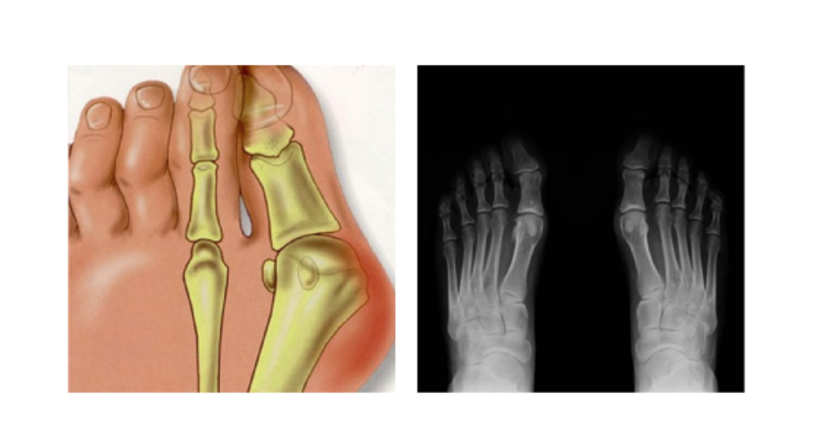

ist eine der häufigsten Fehlbildungen der Zehen. Er entsteht meistens durch das dauerhafte Tragen zu enger oder unbequemer Schuhe. Deshalb leiden Frauen auch deutlich öfter unter einem Hallux valgus als Männer. Die Entstehung eines Ballenzehs, wie die Fehlstellung der Großzehe auch genannt wird, kann aber auch durch ein schwaches Bindegewebe, häufiges Stehen oder Rheuma begünstigt werden. Beim Hallux valgus verschiebt sich der Mittelfußknochen nach außen, wo er einen Ballen ausbildet, der bei manchen Patienten gerötet und geschwollen sein kann. Der große Zeh knickt nach innen zu den mittleren Zehen ab. Bei Berührung haben Patienten Schmerzen in der Großzehe, die auch bis in die kleinen Zehen ausstrahlen können.

Mithilfe von konservativen Therapien lassen sich die Schmerzen verringern und das Fortschreiten des Hallux valgus aufhalten. Rückgängig machen kann man die Fehlstellung aber nur durch eine Operation. Ich habe mich auf die minimal-invasive Fußchirurgie ohne Metallimplantate spezialisiert. Bei einer minimal-invasiven Operation wird der Ballen mit speziellen Operationsinstrumenten über drei winzige Einschnitte beseitigt. Muskeln und anderes Gewebe werden bei dieser Methode geschont, was zu einer schnelleren Rehabilitation nach dem Eingriff führt. Viele Chirurgen verwenden für die Fixierung der Knochen Metallschrauben oder stifte. Diese verursachen oft Probleme beim Patienten und müssen in den meisten Fällen nach der Heilungsphase bei einer Folgeoperation wieder entfernt werden. Aus diesem Grund verwende ich bioresorbierbare Schrauben, die aus gepresstem Zucker hergestellt werden. Einerseits sind diese Implantate leichter verträglich und fördern damit die Heilung. Andererseits lösen sie sich nach zwölf bis achtzehn Monaten auf und ersparen den Patienten dadurch eine Folgeoperation.